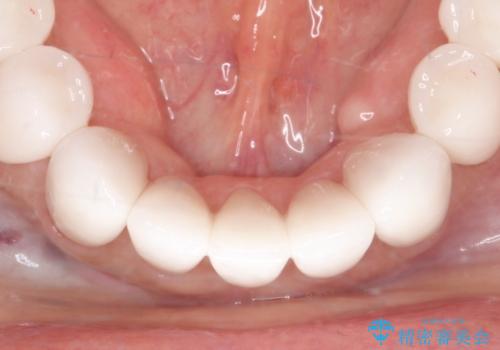

- 昔、他院で治療したダイレクトボンディング(歯の表面にだけ白い材料を盛る治療)のやりかえを主訴に来院されました。叢生の改善も同時に行うためにオールセラミッククラウンにより治療を行いました。

再治療を避けるため、適合精度にこだわり治療を行なっております。

ダイレクトボンディングでの治療より、天然歯に近い見た目を再現することができます。